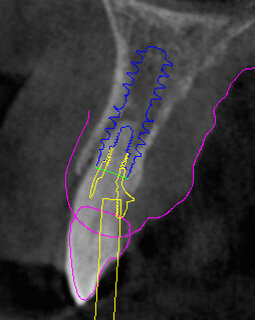

Il piano di trattamento prevede l’estrazione degli elementi dentali, l’inserimento di due impianti e la realizzazione di una protesi fissa di quattro elementi. Il problema da gestire è quello della fase provvisoria. Non è ipotizzabile una protesi mobile e quindi programmiamo di inserire subito dopo l’intervento un provvisorio immediato. Questo ci consente di condizionare da subito i tessuti periimplantari e anche le zone dei ponti. Si rileva un’impronta digitale (Figg. 5, 6), e la programmazione degli impianti viene effettuata con un software di chirurgia guidata (Fig. 7) e la posizione degli impianti nello spazio biologico e nello spazio protesico viene fatta sulla base di una ceratura diagnostica (Figg. 8, 9). Inseriamo gli impianti virtuali nell’osso disponibile (Figg. 10-13) e in relazione all’aspetto protesico correggiamo l’asse di inclinazione degli impianti con componenti secondarie angolate a 17° (Figg. 14, 15). Questo ci consentirà di realizzare una protesi avvitata con i fori situati nella zona palatale.

Fig. 10 - Posizionamento virtuale dell’impianto 1.2.

Fig. 11 - Posizionamento virtuale dell’impianto 2.2.

Fig. 12 - Cross impianto 1.2.

Fig. 13 - Cross impianto 2.2.